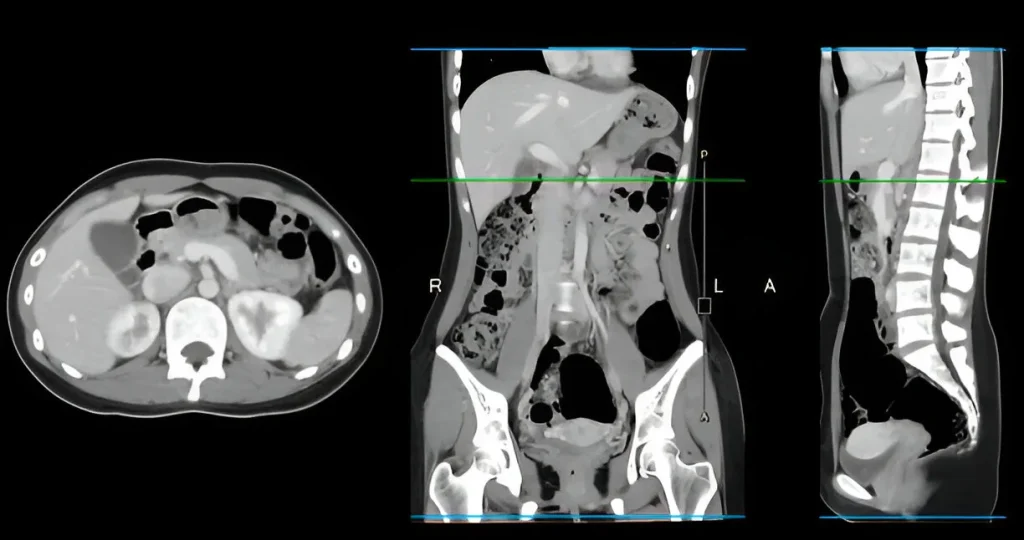

CT Whole Abdomen Scan in Navi Mumbai | Henotic Diagnostics

Looking for a CT Whole Abdomen scan in Kharghar? Henotic Diagnostics offers advanced multi-slice CT scans for the liver, pancreas, kidneys, intestines, spleen, and pelvic organs. Furthermore, this scan helps detect abdominal pain, tumors, infections, kidney stones, liver diseases, and gastrointestinal issues with high precision. In addition, our expert radiologists provide fast reports and accurate results using low-radiation, high-resolution CT technology. Similarly, services are available in Kharghar, Panvel, Belapur, Nerul, Vashi, and Navi Mumbai. Therefore, book your CT Whole Abdomen scan near you today!